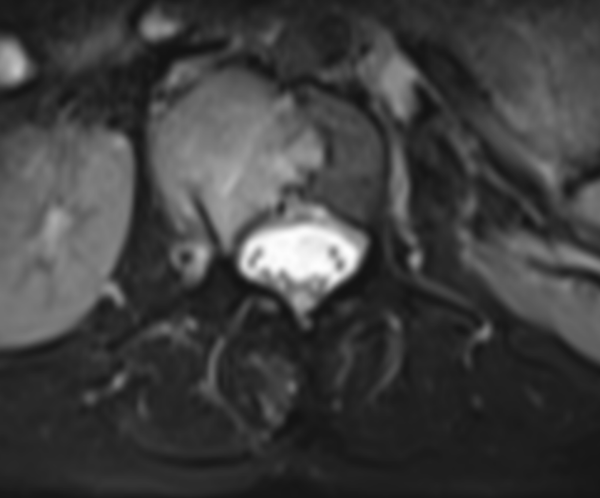

△ 術(shù)前MRI:腰2椎體骨質(zhì)破壞,考慮腫瘤性病變。